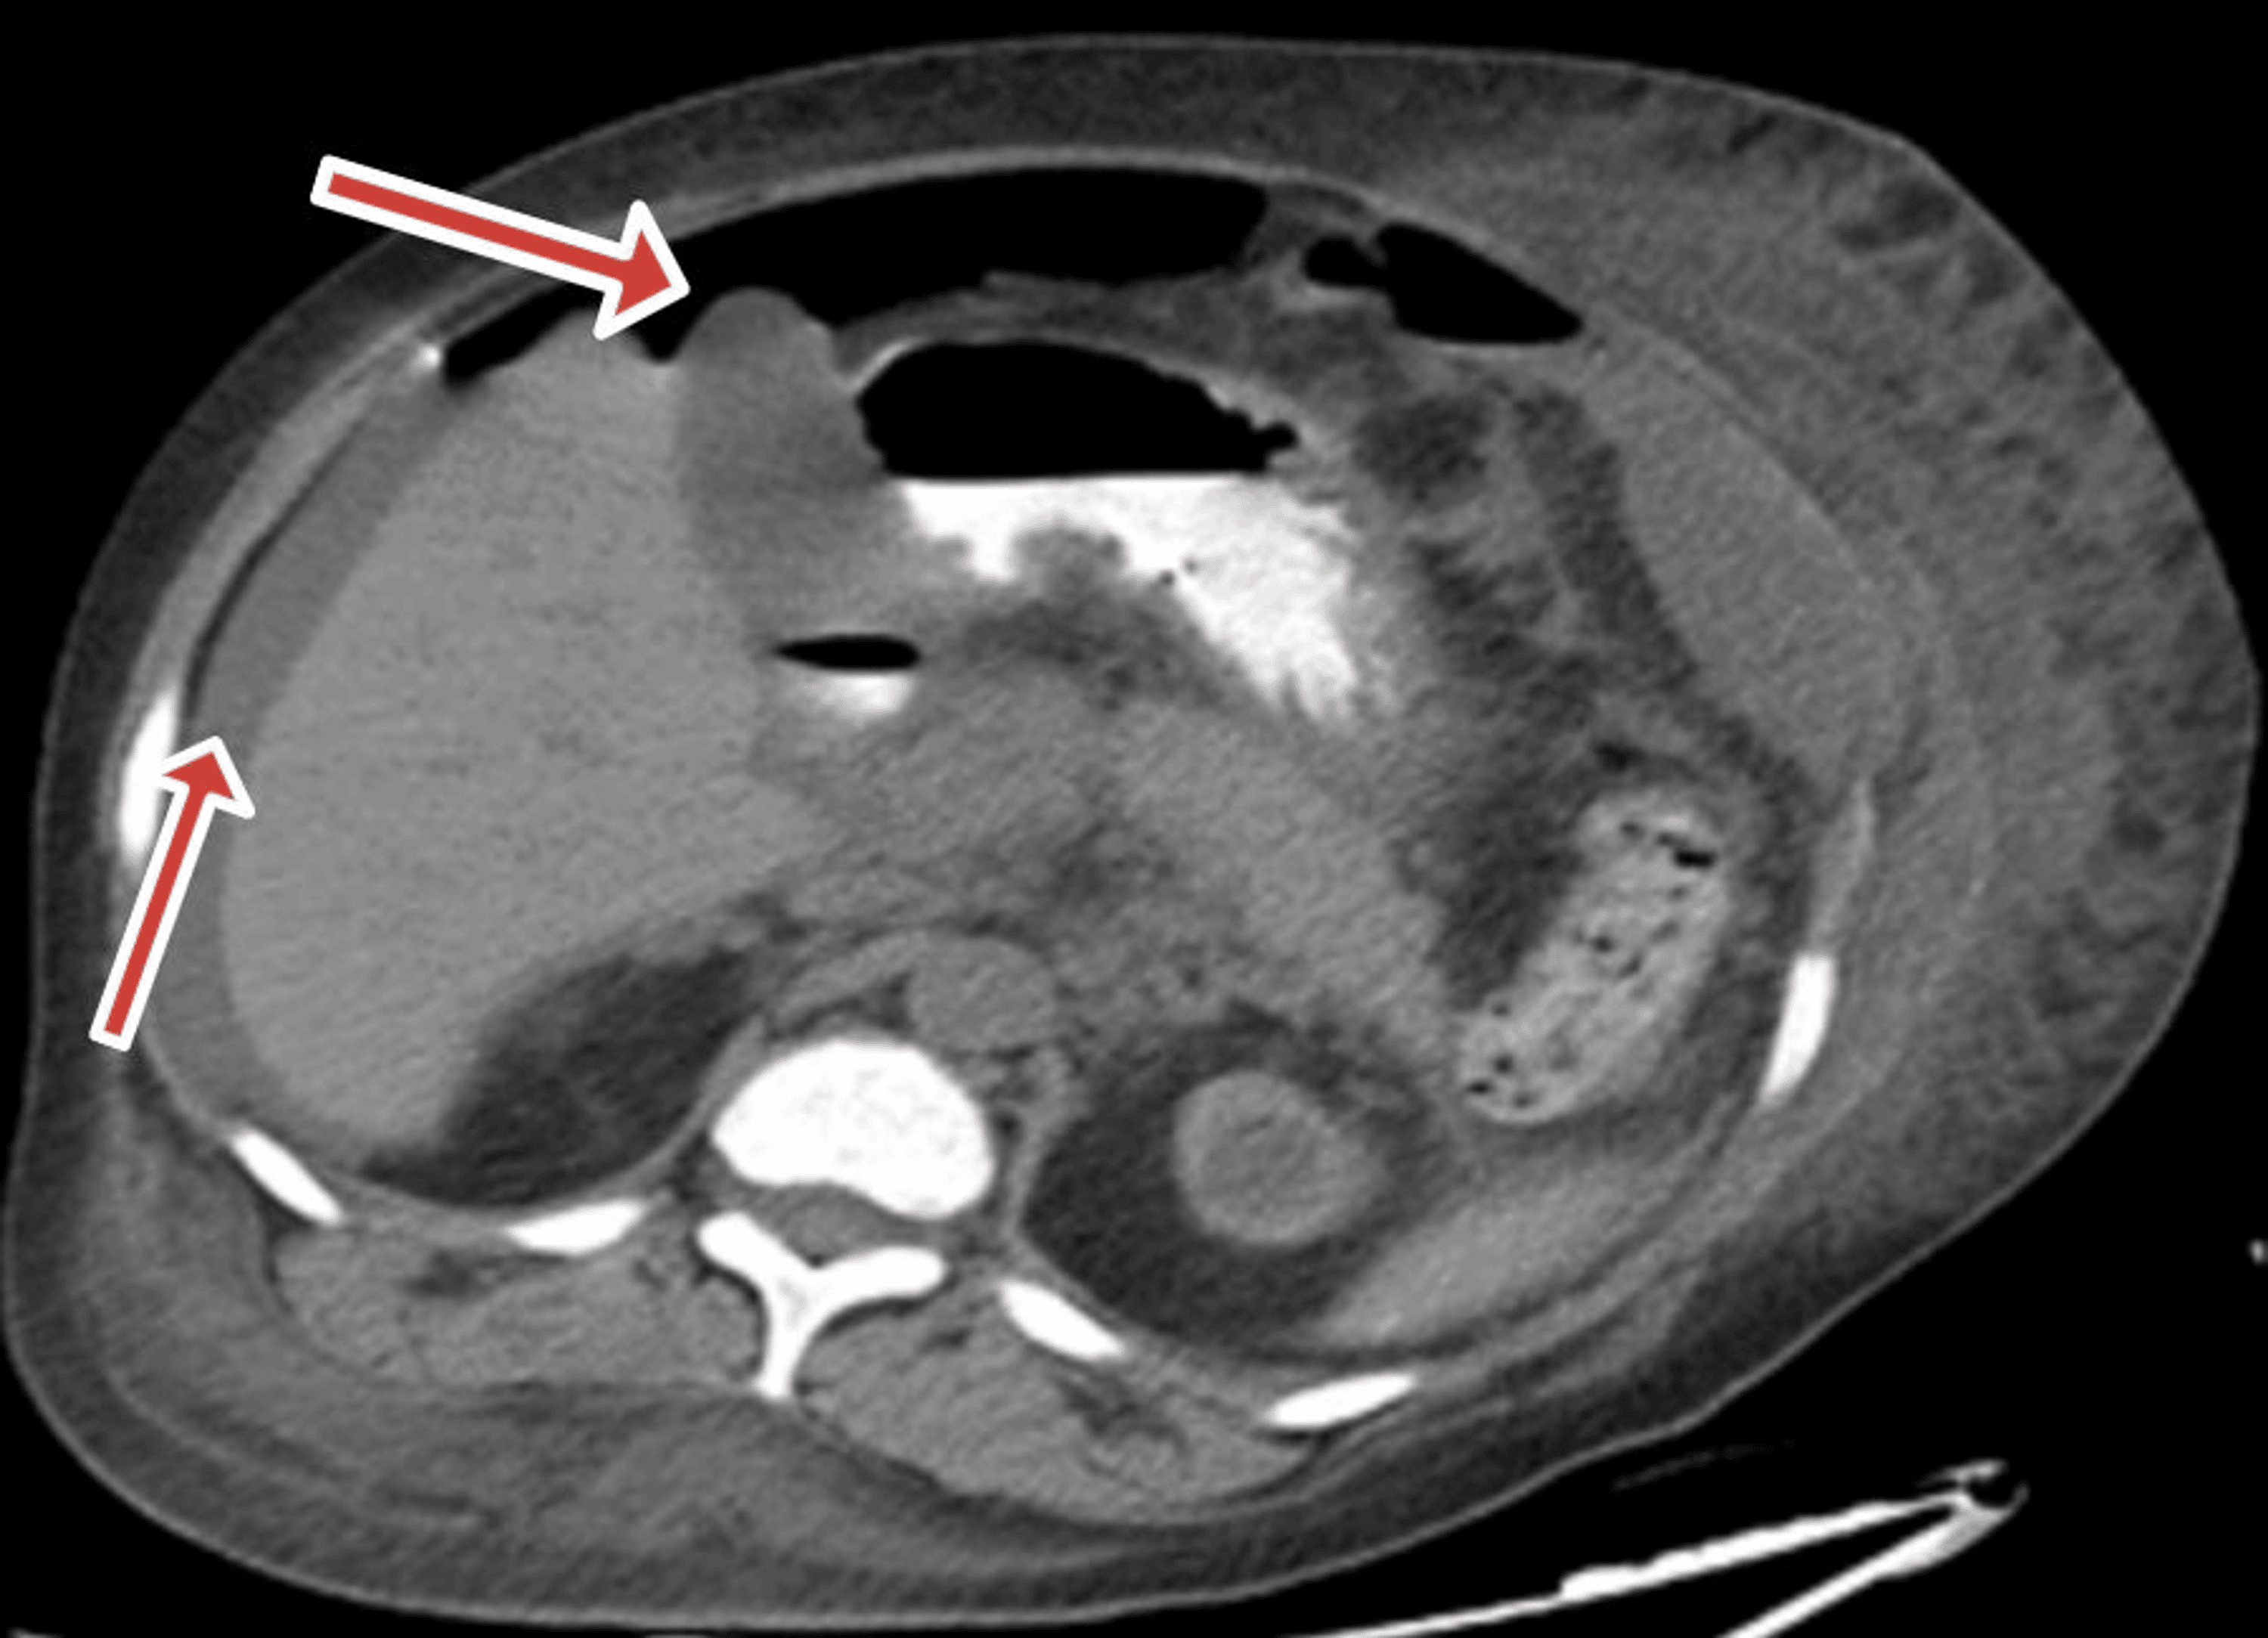

From www.researchgate.net

Ischemic colitis in a critically ill patient. CT scan obtained with... Download Scientific Diagram Ischemic Colitis Lupus Multiple “punched out” ulcers with pale mucosa were not seen in uc but in ischemic colitis and in the colonic involvement of. Ischemic colitis and proctitis is a rare manifestation of systemic lupus erythematosus (sle). Ischemic colitis is a leading cause of acute abdomen in elderly patients. Ischemic colitis is an uncommon complication in patients with systemic lupus erythematosus (sle).. Ischemic Colitis Lupus.